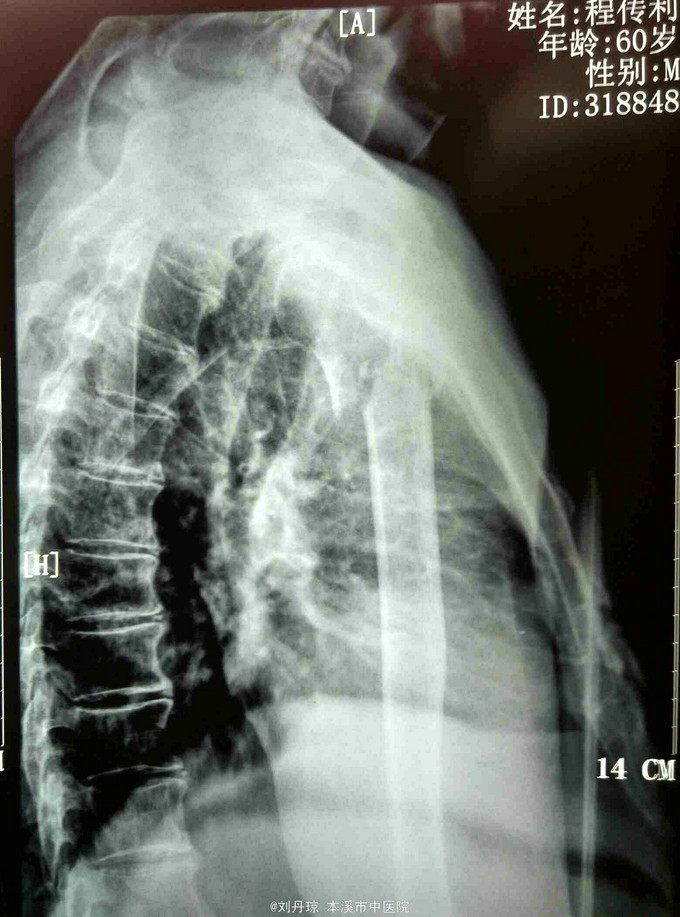

患者男60岁。主诉:左肩刺痛,活动受限2小时。 病史:患者2小时前散步时不慎摔倒,左肩刺痛, 活动受限。伤后由朋友送入我院。

左肩部畸形、肿胀明显,外科颈部压痛阳性,左肩部功能障碍。DR: 左肱骨近端粉碎骨折,分解为四部分,移位明显。

诊断:左肱骨近端粉碎骨折 治疗:手法整复,夹板固定。接骨丹口服。

随访1年。此四部分骨折,肱骨近端四个解剖部分完全分离,肱骨头移向后方,肱骨头血运破坏严重,容易发生缺血坏死。